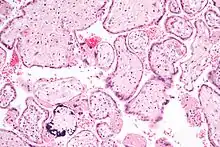

| CMV infection of a human lung pneumocyte | |

CMV infection can be demonstrated microscopically by the detection of intranuclear inclusion bodies. On H&E staining, the inclusion bodies stain dark pink and are called "owl's eye" inclusion bodies.[45]